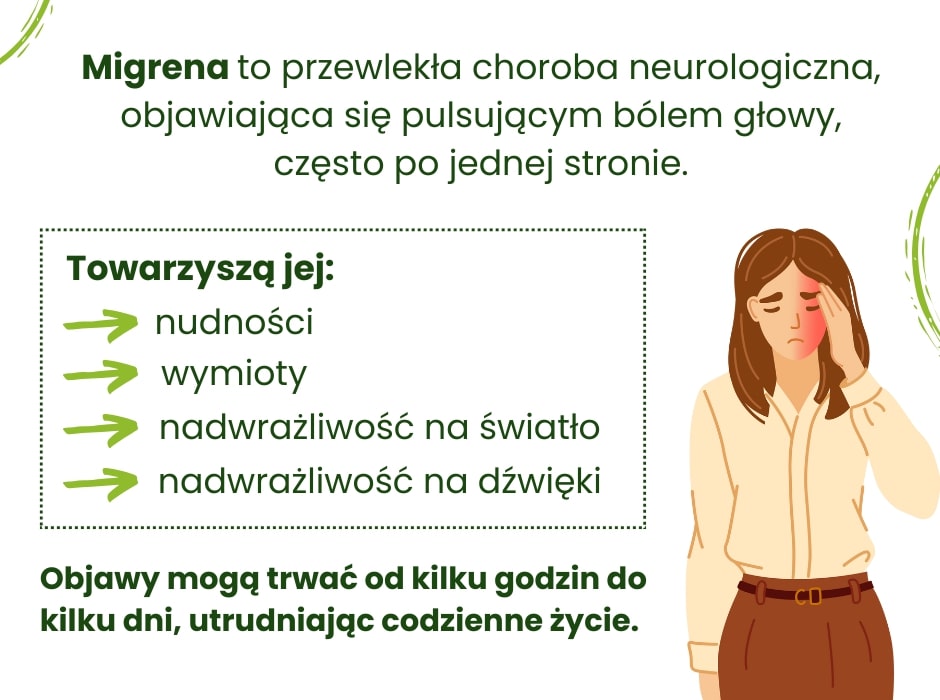

Migrena to przewlekła choroba neurologiczna, której głównym objawem jest intensywny, pulsujący ból głowy, najczęściej odczuwany po jednej stronie. Migrena wykracza jednak poza sam fizyczny ból – wpływa na codzienne życie, obniżając komfort i utrudniając normalne funkcjonowanie. Objawy migreny mogą trwać od kilku godzin do nawet kilku dni, a często towarzyszą im dodatkowe dolegliwości, takie jak nudności, wymioty czy nadwrażliwość na światło, dźwięki i zapachy. W momentach nasilenia migreny nawet najmniejsze aktywności stają się wyzwaniem.

Migrena to nie tylko ból głowy. Często towarzyszą jej dodatkowe objawy, które mogą wywoływać równie duży dyskomfort. Każdy napad może różnić się intensywnością i przebiegiem, ale większość osób odczuwa pulsujący ból, zwykle po jednej stronie głowy. Może to być odczucie tak intensywne, że normalne funkcjonowanie staje się niemożliwe.

Migrena różni się od zwykłych bólów głowy, takich jak napięciowy ból głowy, zarówno charakterem bólu, jak i dodatkowymi symptomami. Przy migrenie ból często jest pulsujący, jednostronny i nasilający się przy aktywności fizycznej. Wiele osób z migreną odczuwa także nudności, wymioty oraz nadwrażliwość na światło i dźwięk.